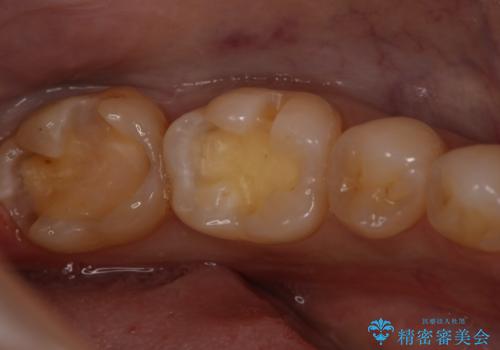

- 左下6、7番の虫歯をセラミックにて治療を希望された患者様です。

切削量を考慮してセラミックインレーを選択しました。

7番は虫歯が深かったのでCR裏層した上で形成、印象をしています。